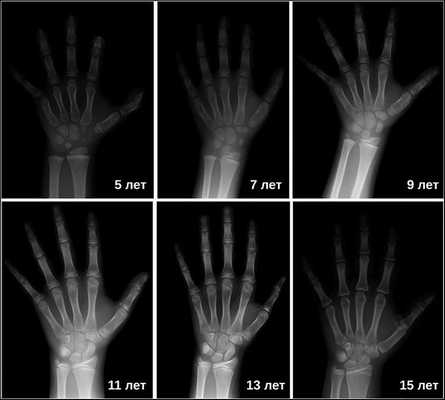

Затем врачи определяют костный возраст. Сделать это можно с помощью рентгена или УЗИ запястья. В норме костный возраст может отставать или опережать паспортный на два года.

Рентгенография турецкого седла выявляет его детскую форму («стоячий овал») и широкую (т. н. ювенильную) спинку. При увеличении размеров турецкого седла и наличии участков обызвествления, в первую очередь, следует думать об опухоли. Рентгенография лучезапястных суставов и кистей позволяет определить рентгенологический («костный») возраст. При гипофизарном нанизме отмечается значительное замедление процессов окостенения скелета.